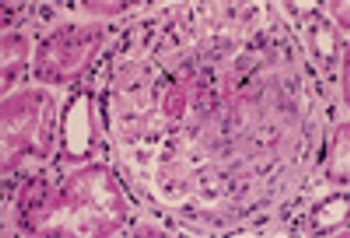

A 56-year-old was seen in the ED after 4 days of hemoptysis and intermittent left chest pain. He also complained of exertional dyspnea and arthralgias. He had been treated for “pneumonia” twice during the past month. Histories were unremarkable.